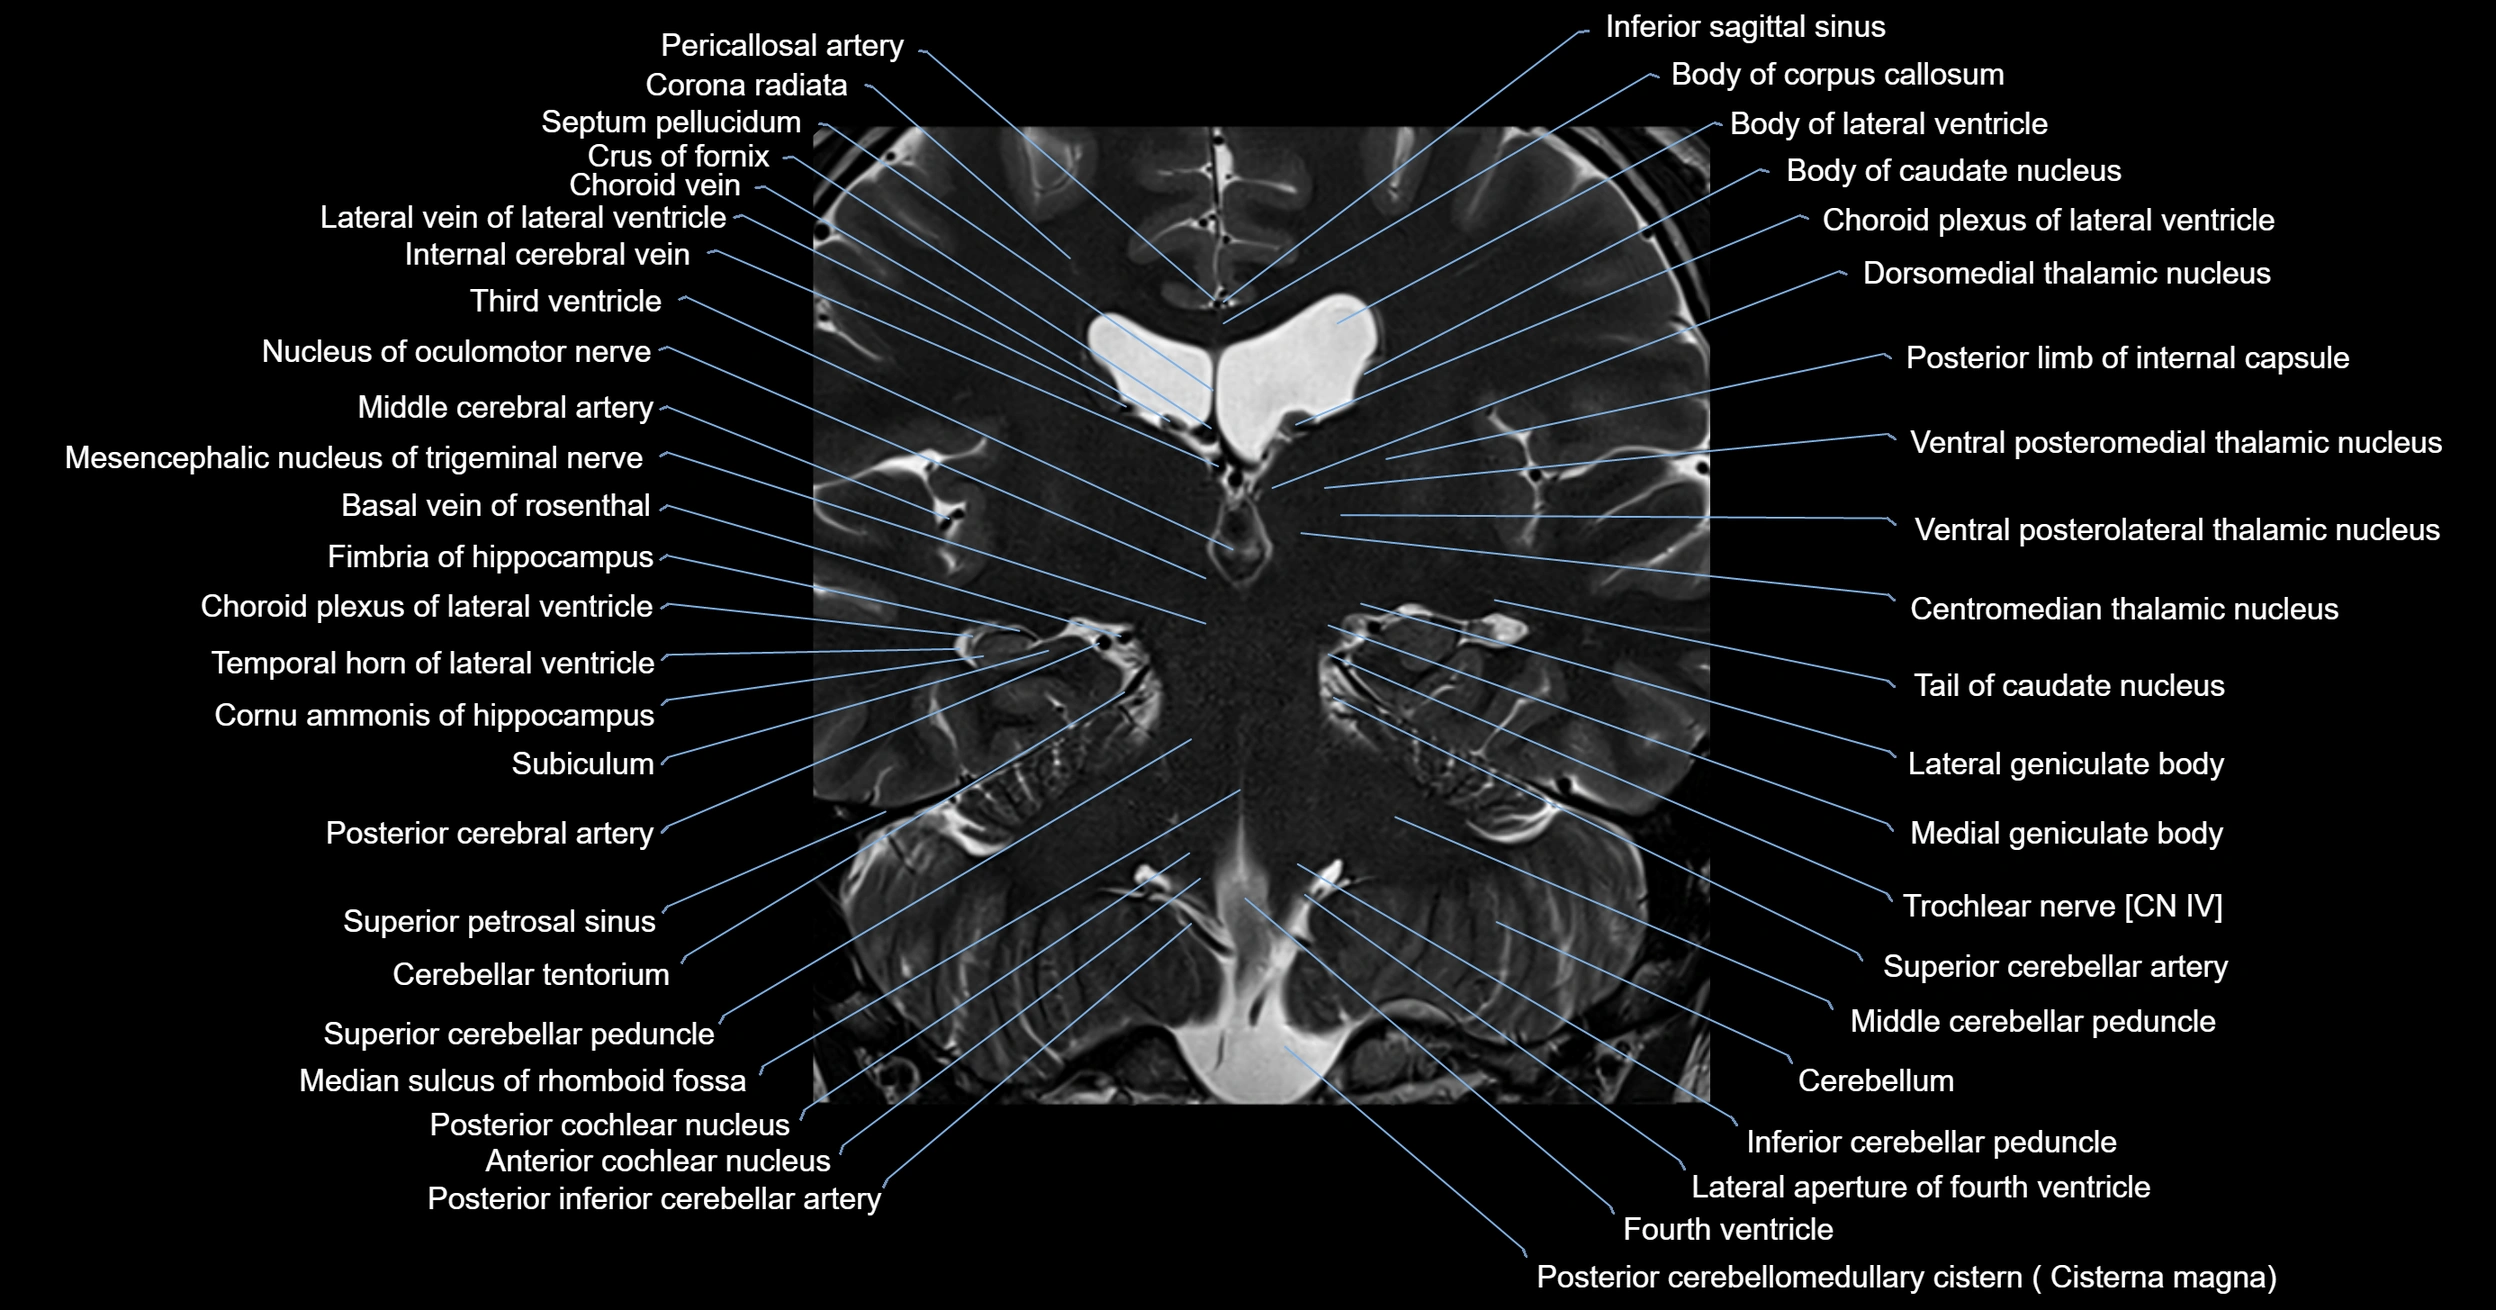

- Ambient cistern

- Anterior cochlear nucleus

- Basal vein of rosenthal

- Cerebellar tentorium

- Cerebellum

- Choroid plexus of fourth ventricle

- Choroid plexus of the lateral ventricle

- Dorsal cochlear nucleus

- Fourth ventricle

- Inferior cerebellar peduncle

- Inferior sagittal sinus

- Lateral geniculate body

- Medial geniculate body

- Median sulcus of rhomboid fossa

- Middle cerebellar peduncle

- Posterior cerebellomedullary cistern (cisterna magna)

- Posterior cochlear nucleus

- Posterior inferior cerebellar artery

- Pulvinar

- Superior cerebellar peduncle

- Superior petrosal sinus

- Tail of caudate nucleus

- Tegmentum of midbrain

- Temporal horn of lateral ventricle

- Tonsil of cerebellum

- Trochlear nerve (Cranial nerve IV)